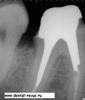

Л Ю С Я Опубликовано 25 марта, 2013 Поделиться Опубликовано 25 марта, 2013 (изменено) Сегодня собрала несколько СИЦ на работе и сделала Р-снимке:оказались все рентгеноконтрастны! Глассин-рест http://ib3.keep4u.ru/s/2013/03/25/25/2508bb9211e3063f4e91446de2d5357f.jpg Фуджи http://ib3.keep4u.ru/s/2013/03/25/60/6001b44958dd590cabe8d7e9e7968656.jpg Витремер http://ib2.keep4u.ru/s/2013/03/25/c8/c84b2541635d866bcf442cca8fa7cede.jpg аквамерон http://ib2.keep4u.ru/s/2013/03/25/b5/b5a316946eb494d7c63aa6ed9bef6964.jpg Изменено 25 марта, 2013 пользователем Л Ю С Я Ссылка на комментарий

Ico Опубликовано 25 марта, 2013 Поделиться Опубликовано 25 марта, 2013 Сегодня собрала несколько СИЦ на работе и сделала Р-снимке:оказались все рентгеноконтрастны! Глассин-рест http://ib3.keep4u.ru/s/2013/03/25/25/2508bb9211e3063f4e91446de2d5357f.jpg Фуджи http://ib3.keep4u.ru/s/2013/03/25/60/6001b44958dd590cabe8d7e9e7968656.jpg Витремер http://ib2.keep4u.ru/s/2013/03/25/c8/c84b2541635d866bcf442cca8fa7cede.jpg аквамерон http://ib2.keep4u.ru/s/2013/03/25/b5/b5a316946eb494d7c63aa6ed9bef6964.jpgЛюся.Если вы их в канал в нужном объеме заведете,выставите экспозицию в 0.8 - 0.12,то посмотрите.Я ж не с потолка так утверждаю.Кетак,Кормакс,Фуджи 1 и для преэндо еще используют "Блокаут". Ссылка на комментарий

Л Ю С Я Опубликовано 25 марта, 2013 Поделиться Опубликовано 25 марта, 2013 (изменено) Из интернета стырилВнимательно посмотрите: в 2.1 пора а в 1.1 нет. В моляре в дист ОК в мед нет. Я не думаю что в моляре в разных каналах разный сиц и поэтому рентгеноконтрастность неодинаковая Изменено 25 марта, 2013 пользователем Л Ю С Я Ссылка на комментарий